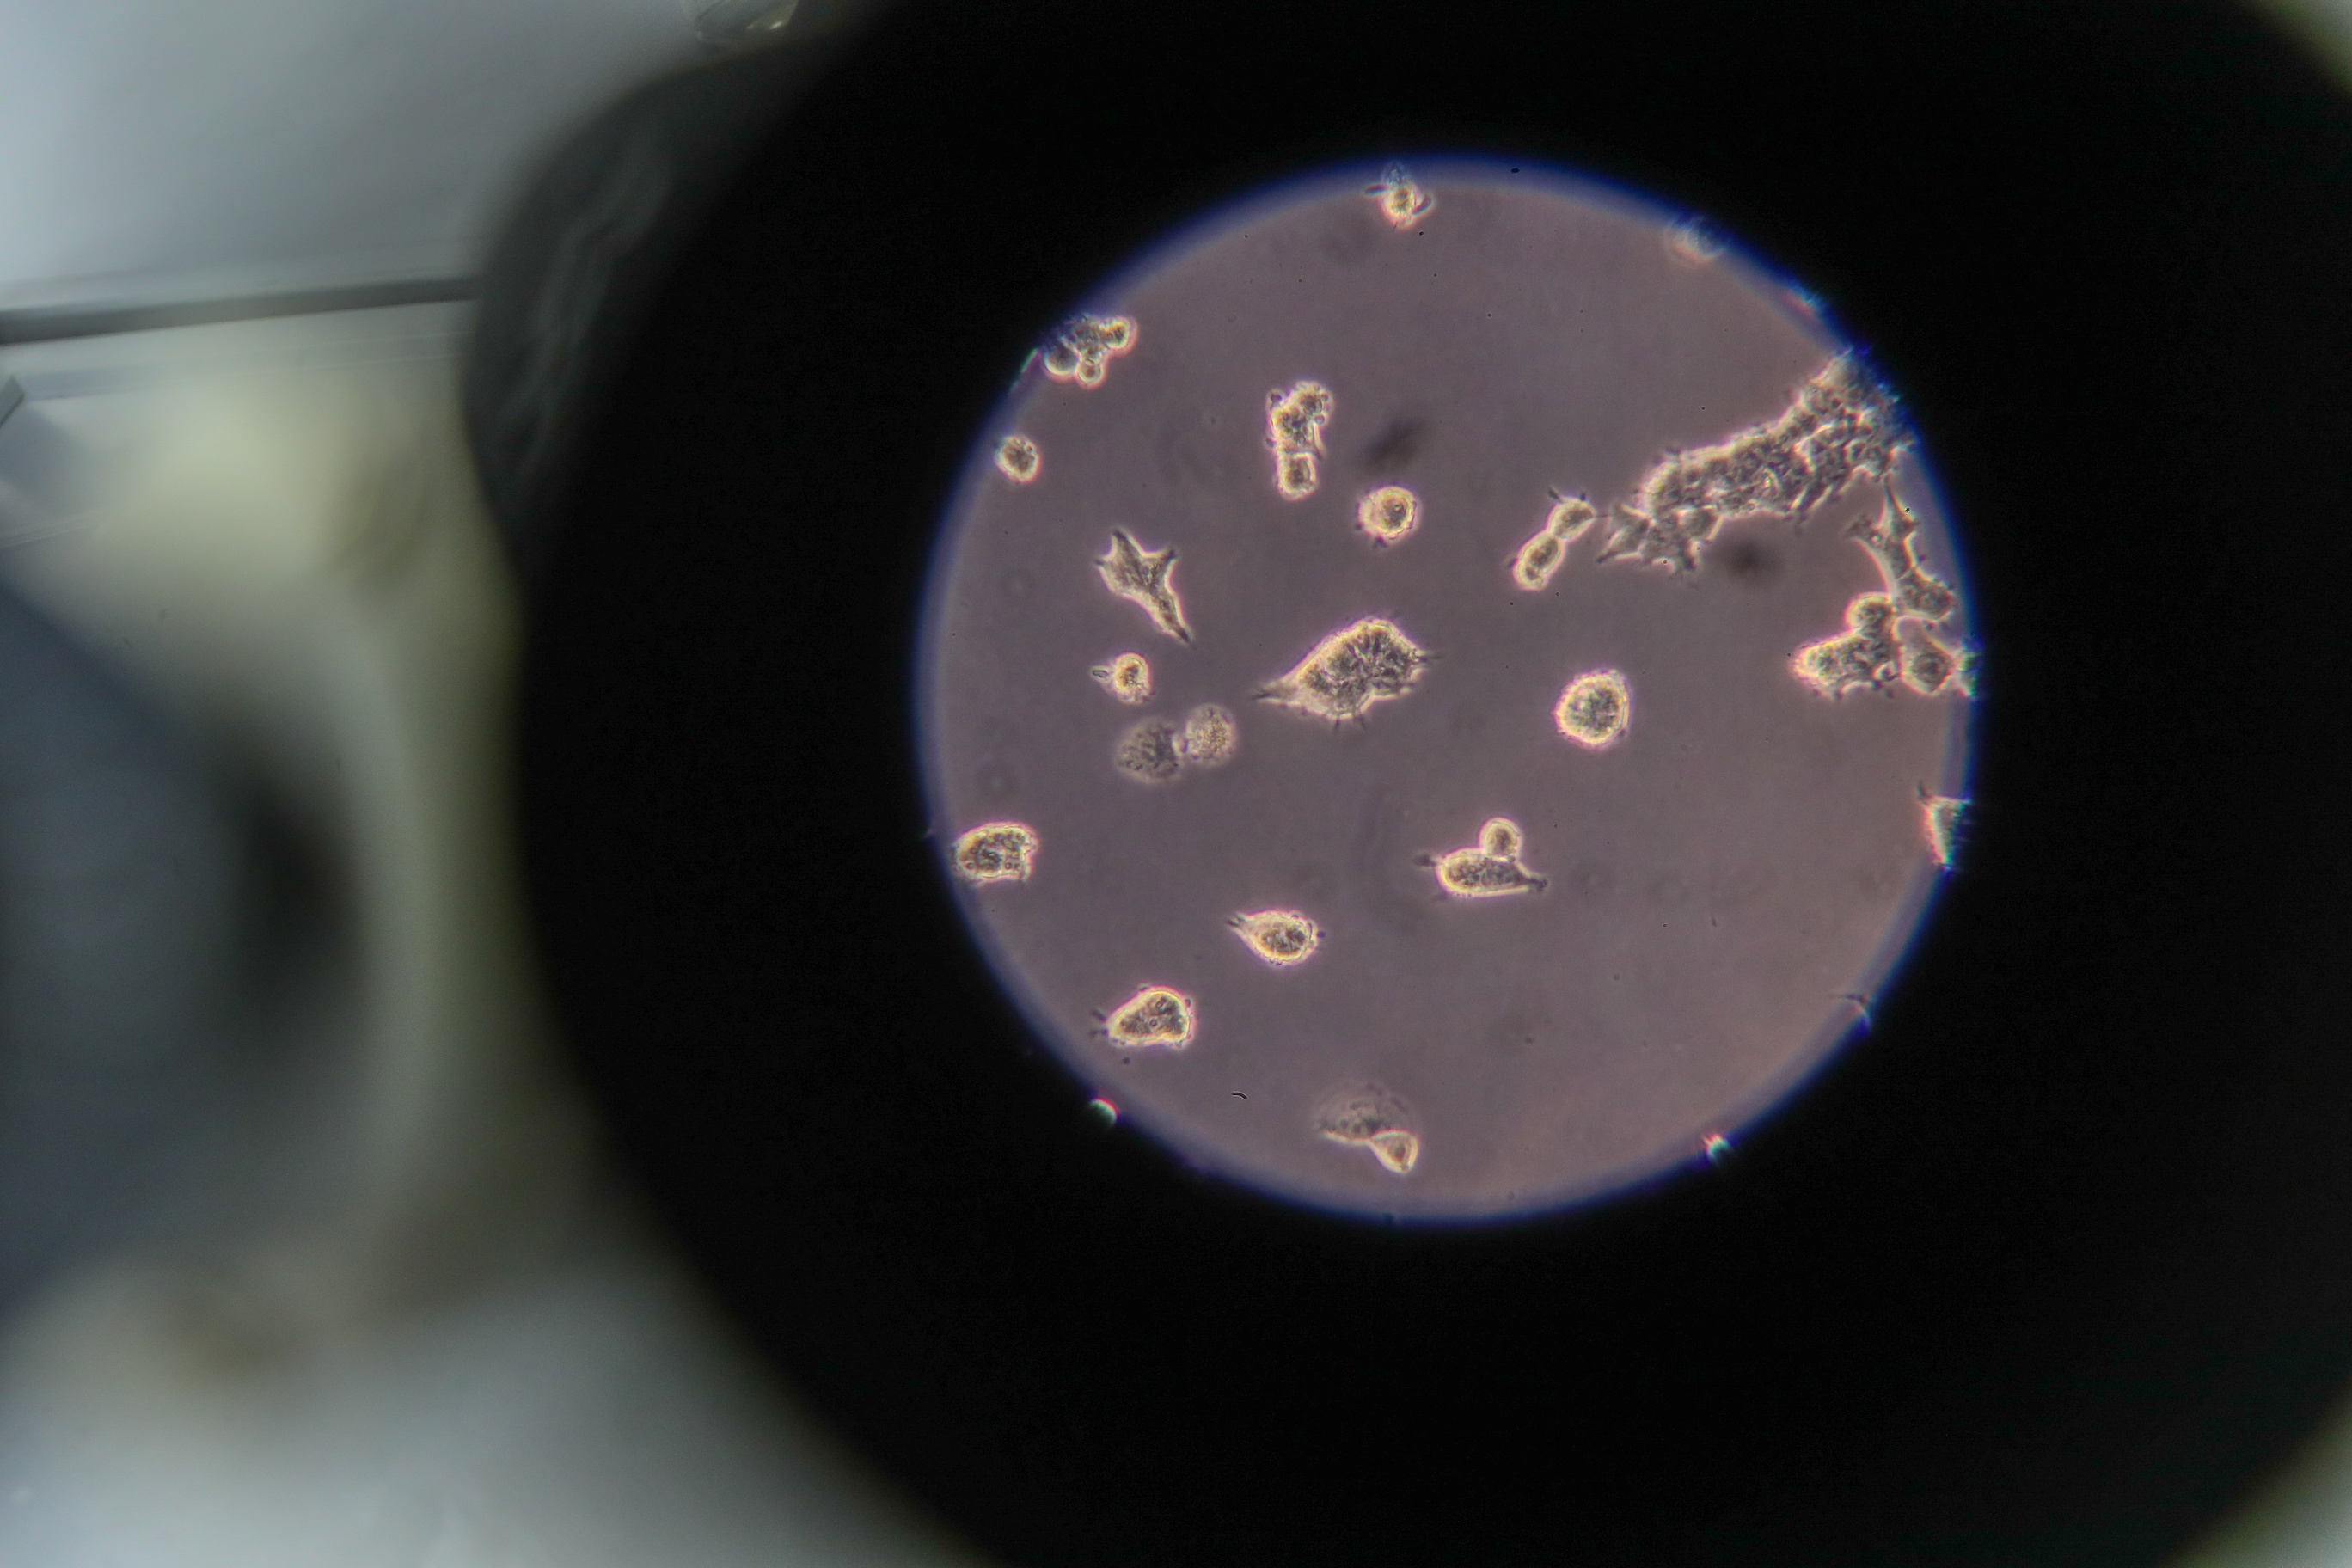

The subsequent experiments demonstrated that the virus indeed is capable of binding to cholesterol but not to the molecules similar to it, and also unexpectedly discovered that the same part of the S-protein that interacts with ACE2 was involved. Encountering this property of the virus, the scientists decided to see what happens if large amounts of cholesterol and lipoprotein are added to the culture medium with cells infected with the SARS-CoV-2 virus.

These experiments confirmed that cholesterol and the receptors recognizing it play an important role in the process of the virus penetrating healthy cells. The more of its molecules were present in the culture medium, the quicker SARS-CoV-2 infected new victims. At the same time, blocking SR-B1 using the ITX 5601 preparation sharply curbed the spread of the virus.